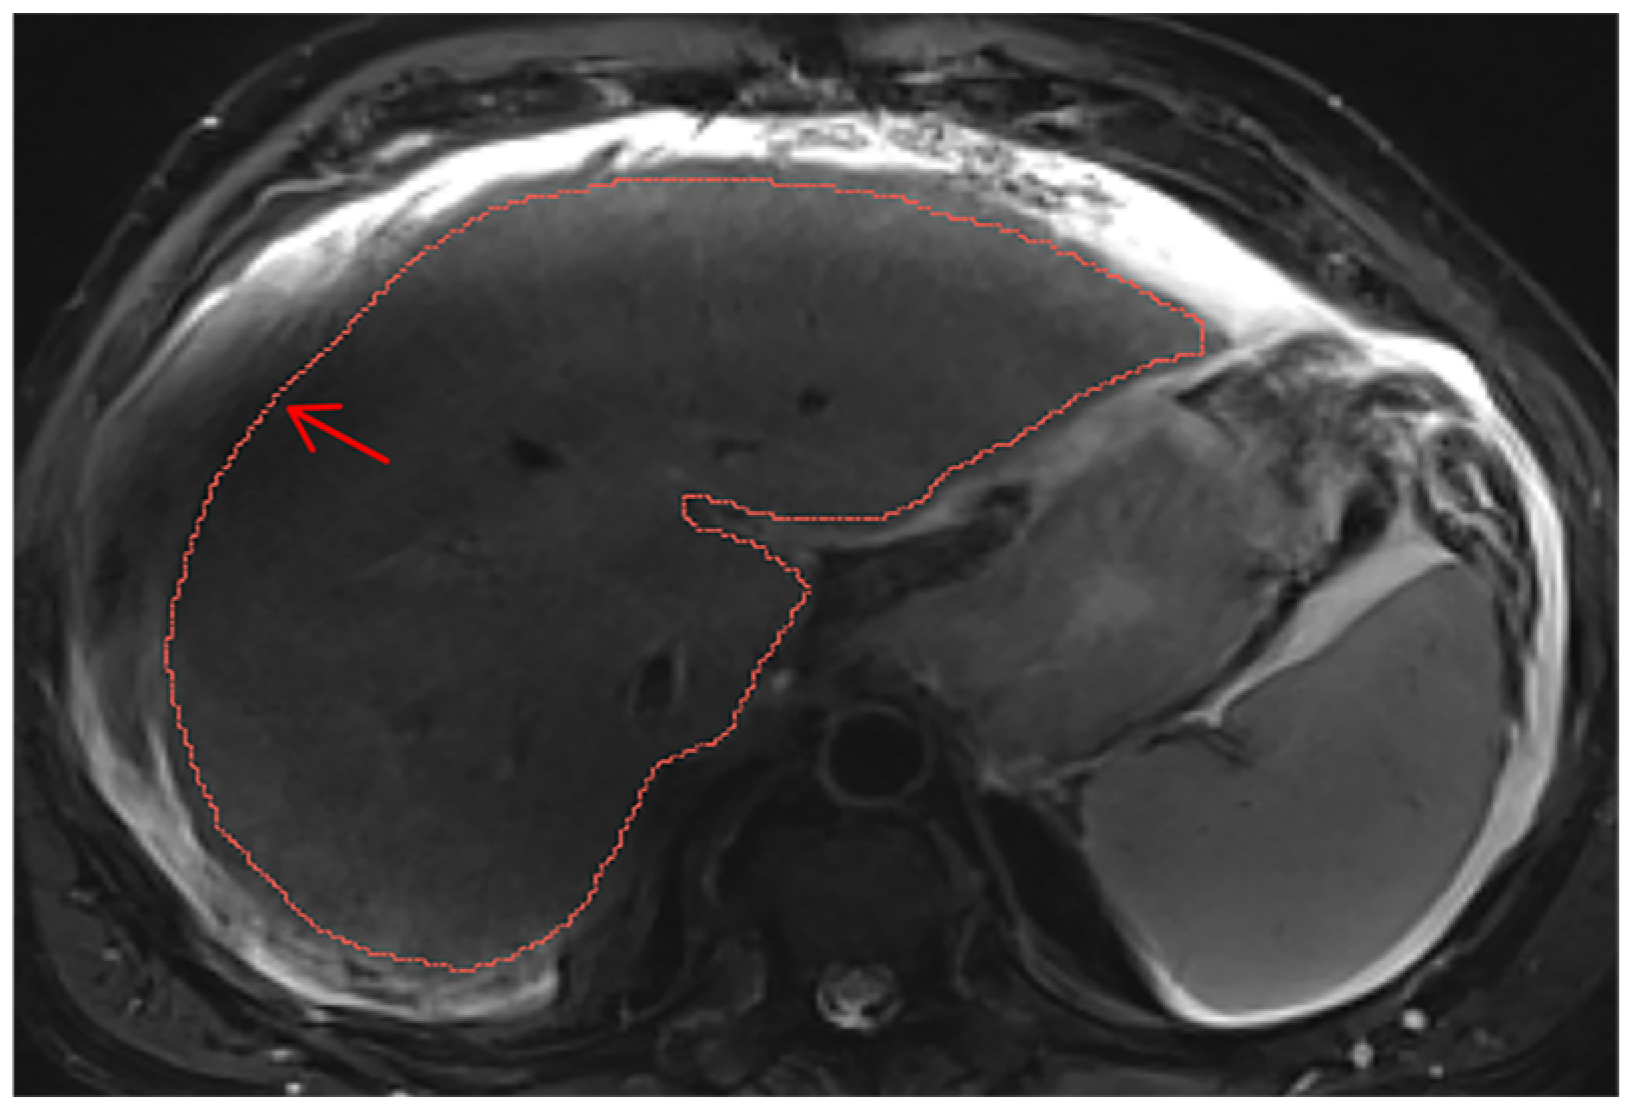

2.2. Liver Segmentations and Protocol

Appendix A.2. Hepatic Hilum Segmentation

Appendix A.7. Ascites